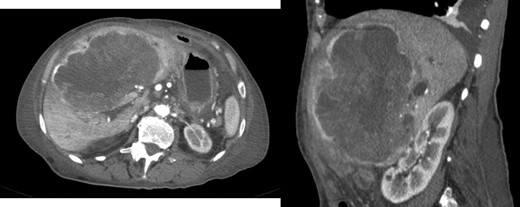

A 78-year-old woman with past medical history of hypertensive cardiopathy and bearer of a pacemaker, was referred to our Hepatobiliary Unit with diagnose of a liver mass discovered on CT scan, which was performed after complaints of nausea and postprandial infarction. CT scan (Fig. 3) showed a voluminous heterogeneous, lobed mass, displaying heterogeneous uptake contrast, relatively vascularized, localized in segment 1, with exophytic growth to the left lobe, with 18.5 × 13.8 × 15.6 cm; the tumor caused deviation of the stomach to the left.

AP-CT – voluminous heterogeneous mass in segment 1 with 18.5 cm in diameter.